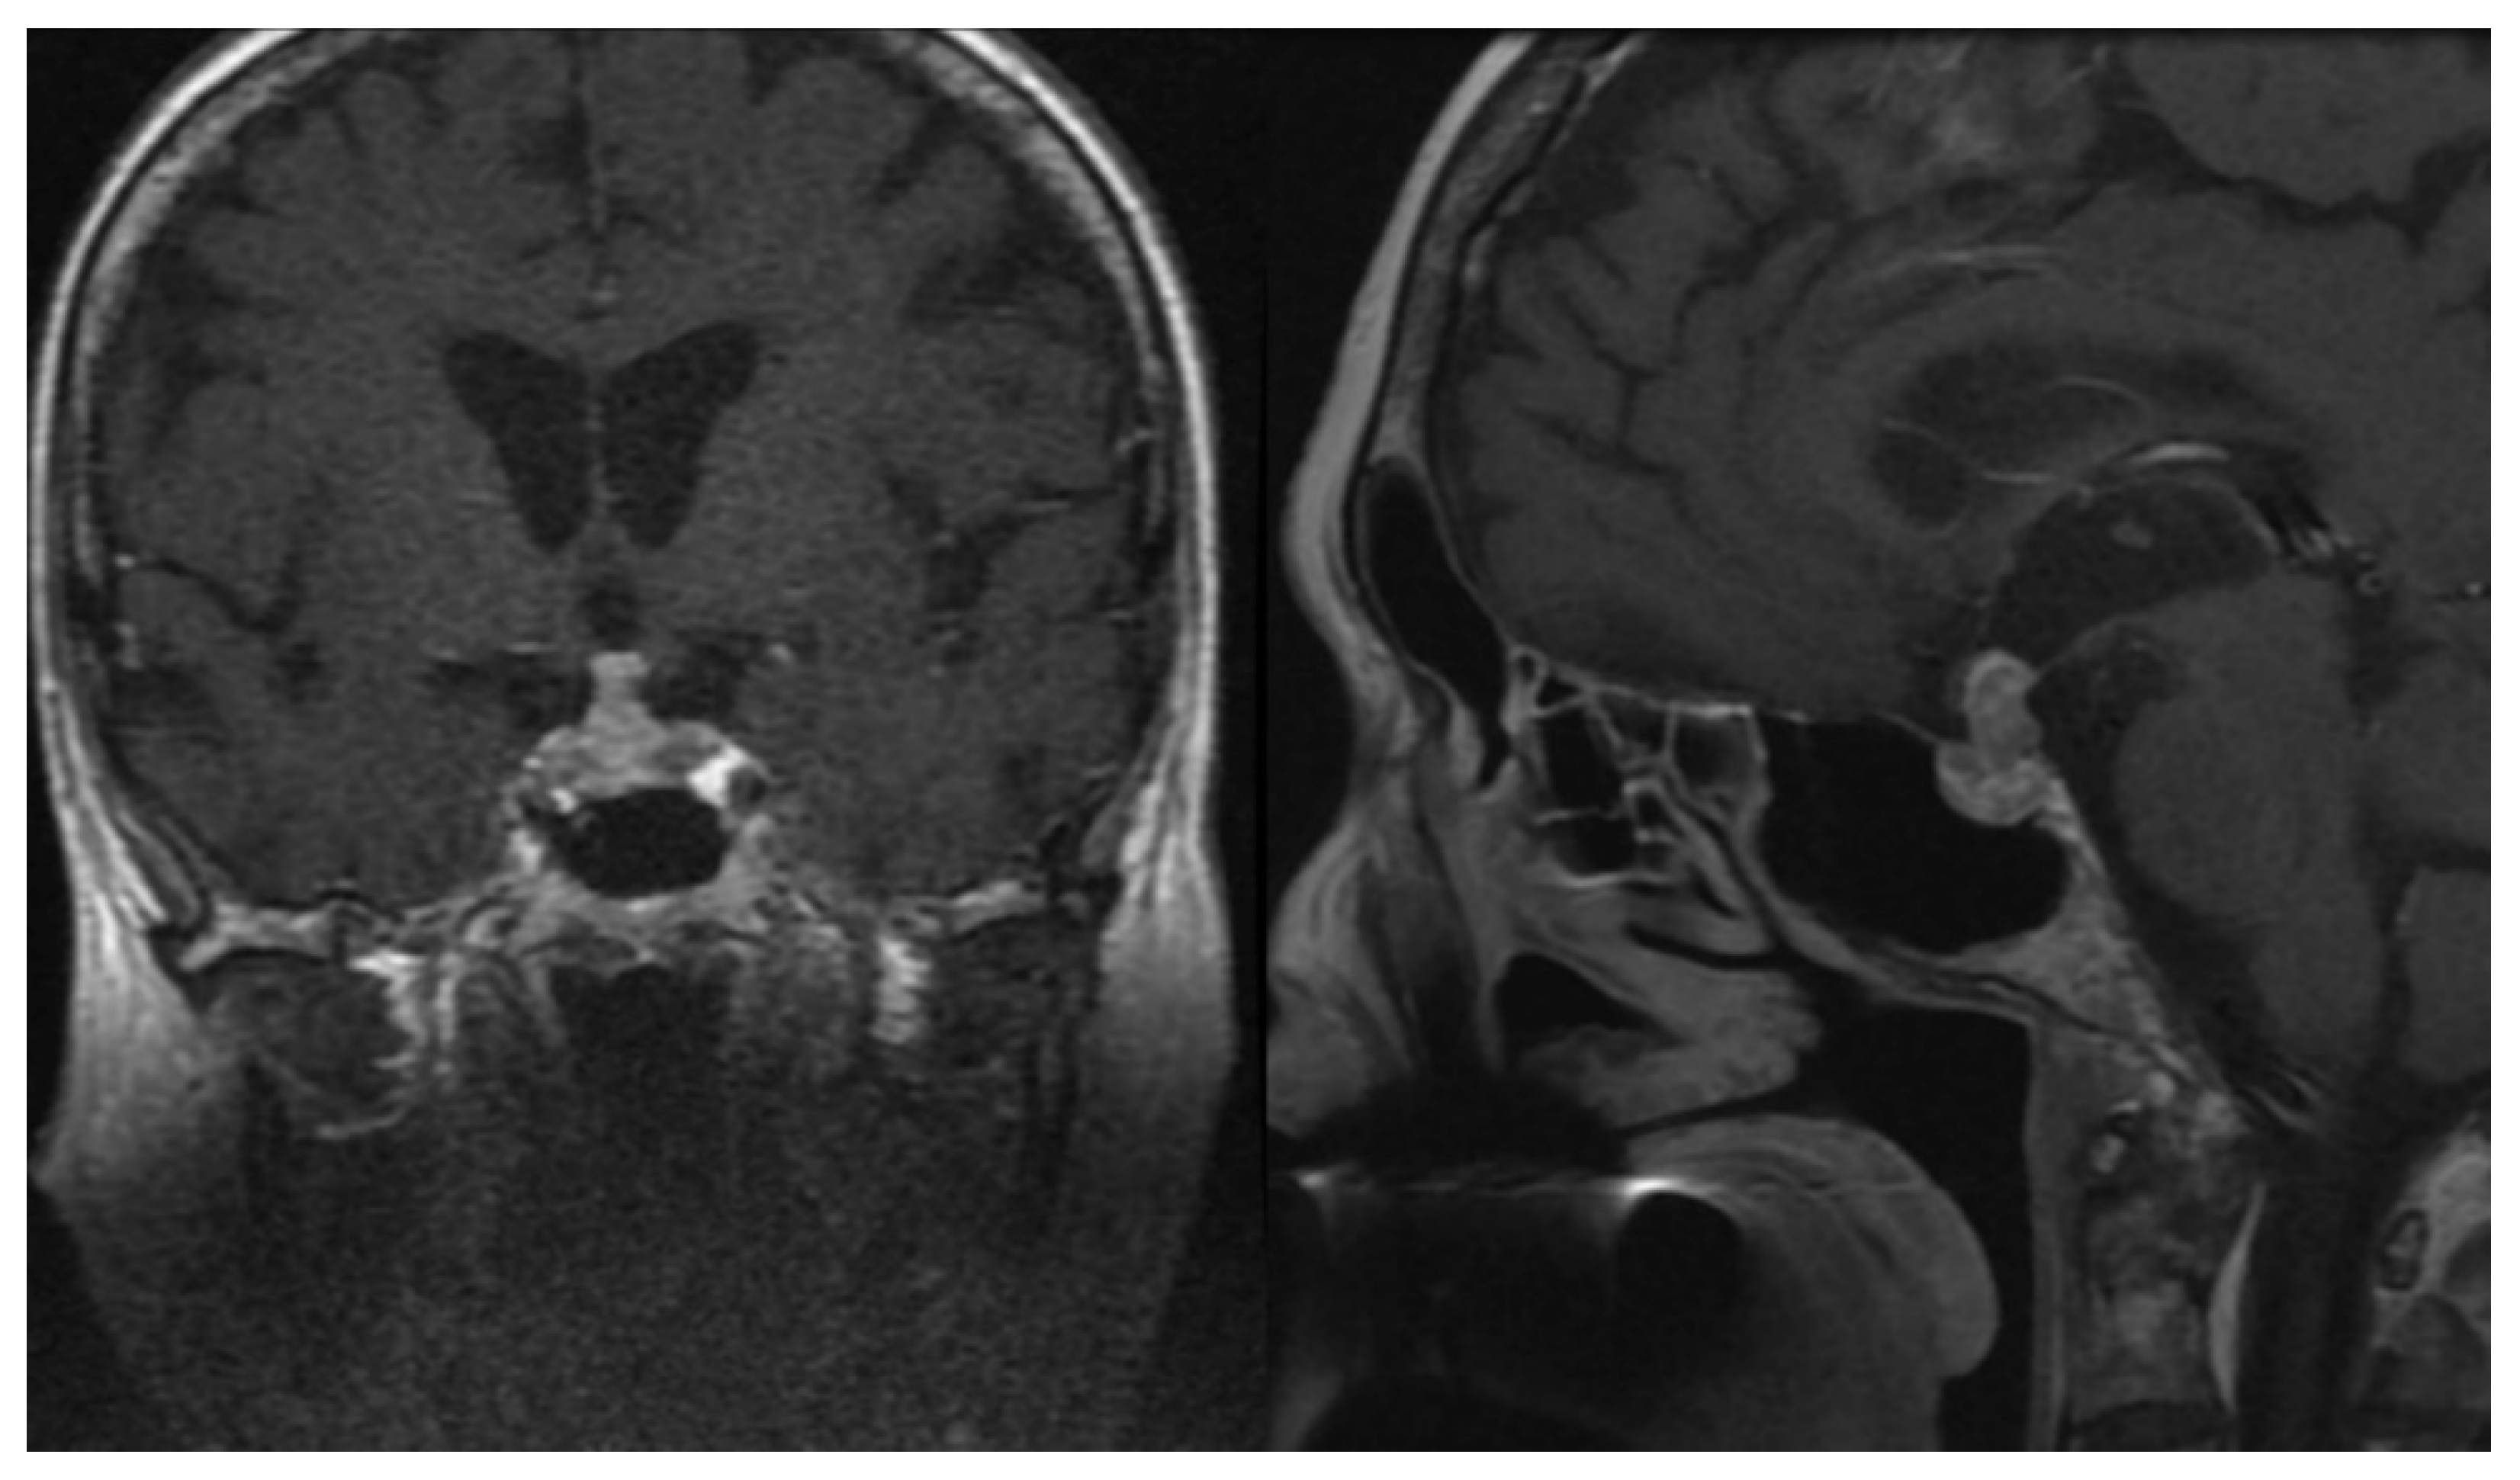

3.4. Imaging